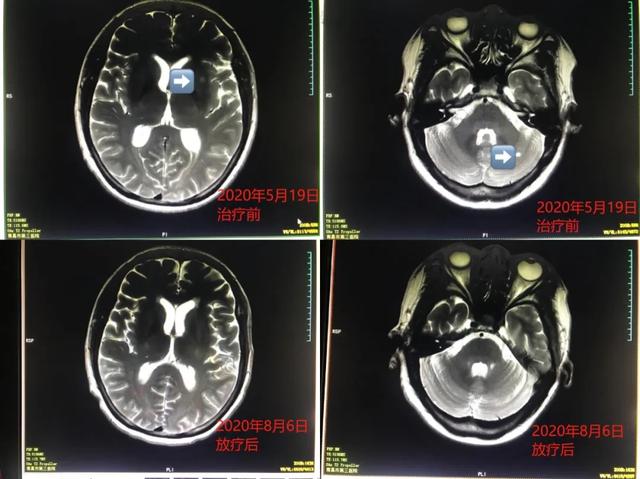

一位乳腺癌脑转移患者,放疗后颅内病灶全消失。